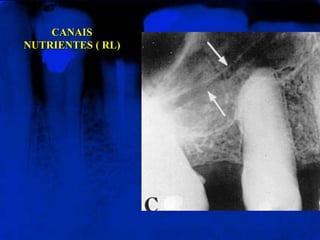

CANAIS  NUTRENTES  ( RL)Vistos como linhas radiolúcidas, que correspondem aos trajetos intra-ósseos das arteríolas ou veias.